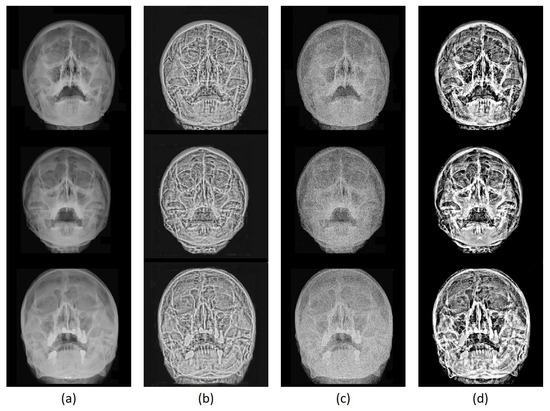

3.3. Image Enhancement Evaluation

3.3.2. Qualitative Evaluation